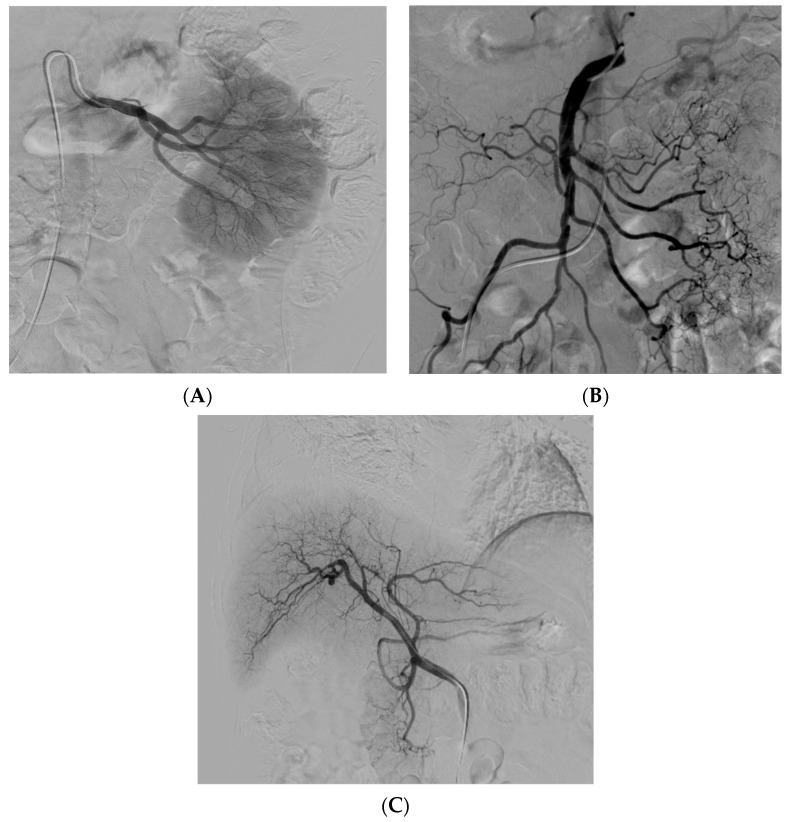

經(jīng)動脈干細(xì)胞注射(TASI)可能被認(rèn)為是一種理想的選擇性遞送方法,在所需器官中具有最佳分布和高干細(xì)胞濃度。在組織取樣和干細(xì)胞分離處理(自體或異體)之后,該過程基本上包括通過動脈通路(最常見的是股動脈)引入導(dǎo)管。然后,在熒光鏡和造影劑引導(dǎo)下,將導(dǎo)管放置在所需的供血動脈(肝動脈、腸系膜動脈或腎動脈)中,以進(jìn)行隨后的干細(xì)胞注射。圖2)。

導(dǎo)管定位確保對所需組織進(jìn)行選擇性治療,避免非目標(biāo)干細(xì)胞輸注。